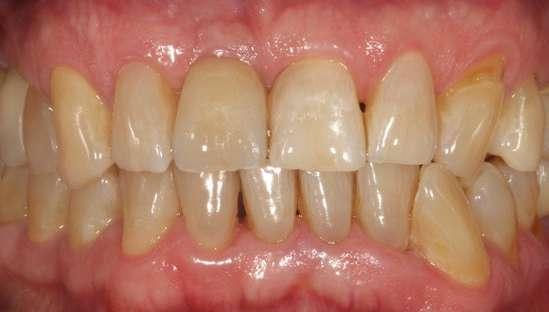

Presentamos el caso de un paciente masculino de 61 años de edad, bruxista, con evidentes desgastes en toda la dentición y cracks de esmalte que pueden observarse en las fotografías iniciales de la primera visita (figuras 1 y 2). En las fotografías

Figuras 1 y 2. Imágenes intraorales de la primera visita donde se hacen evidentes diferentes desgastes en los dientes anteriores y a mayor detalle crakcs en el esmalte, así como lesiones por abfracción en los cuellos de los dientes de los premolares y caninos superiores.